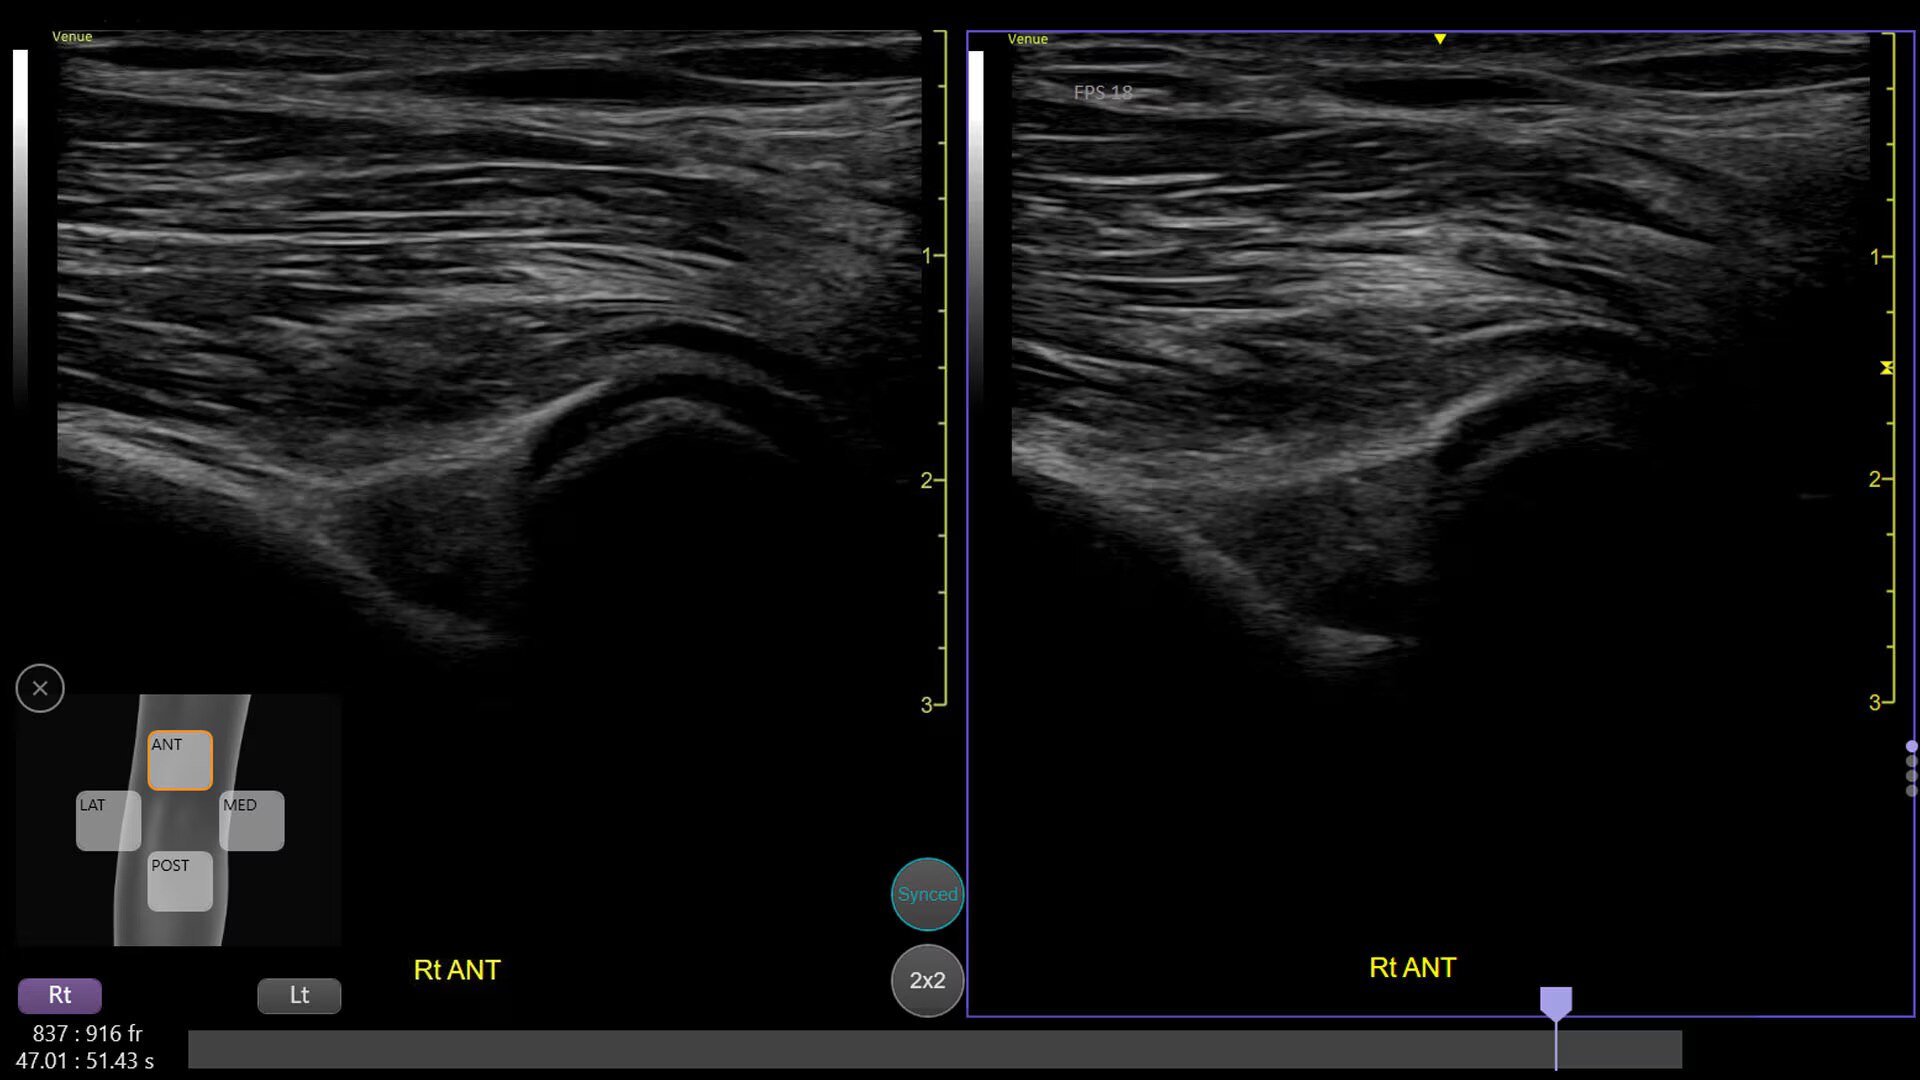

Simplify your workflow with AI-enabled clinical tools.

Helping drive consistency from user to user (whether one is an ultrasound novice or expert), Venue Fit features AI-enabled resources that help clinicians work smarter and more efficiently. Utilizing proprietary algorithms, we synthesize data from numerous patients to ensure accurate calculations for clinical confidence.